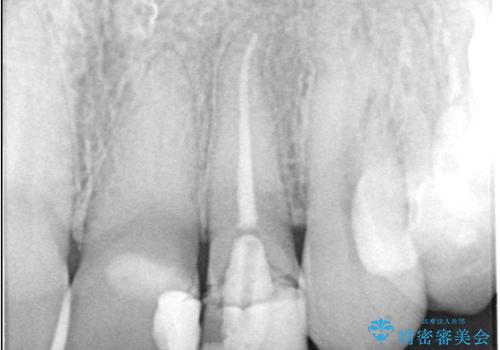

左上2番の唇側歯頚部が欠けており、根管治療を受けている歯でした。

レントゲン写真撮影を行ったところ、歯の中の土台が外れ欠けている状態でしたので土台と被せものの治療を行うこととしました。

外れ欠けている土台をまずやり替えた後、根管治療後の緊密な封鎖を目的としオールセラミッククラウンをセットしました。